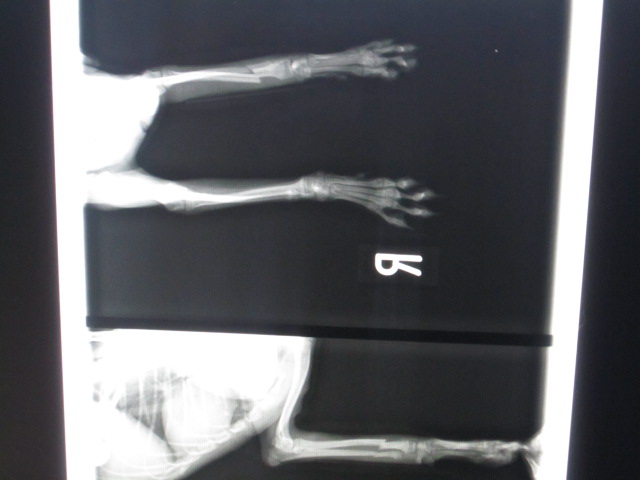

術後のレントゲンです。

今回はピンで整復しました。